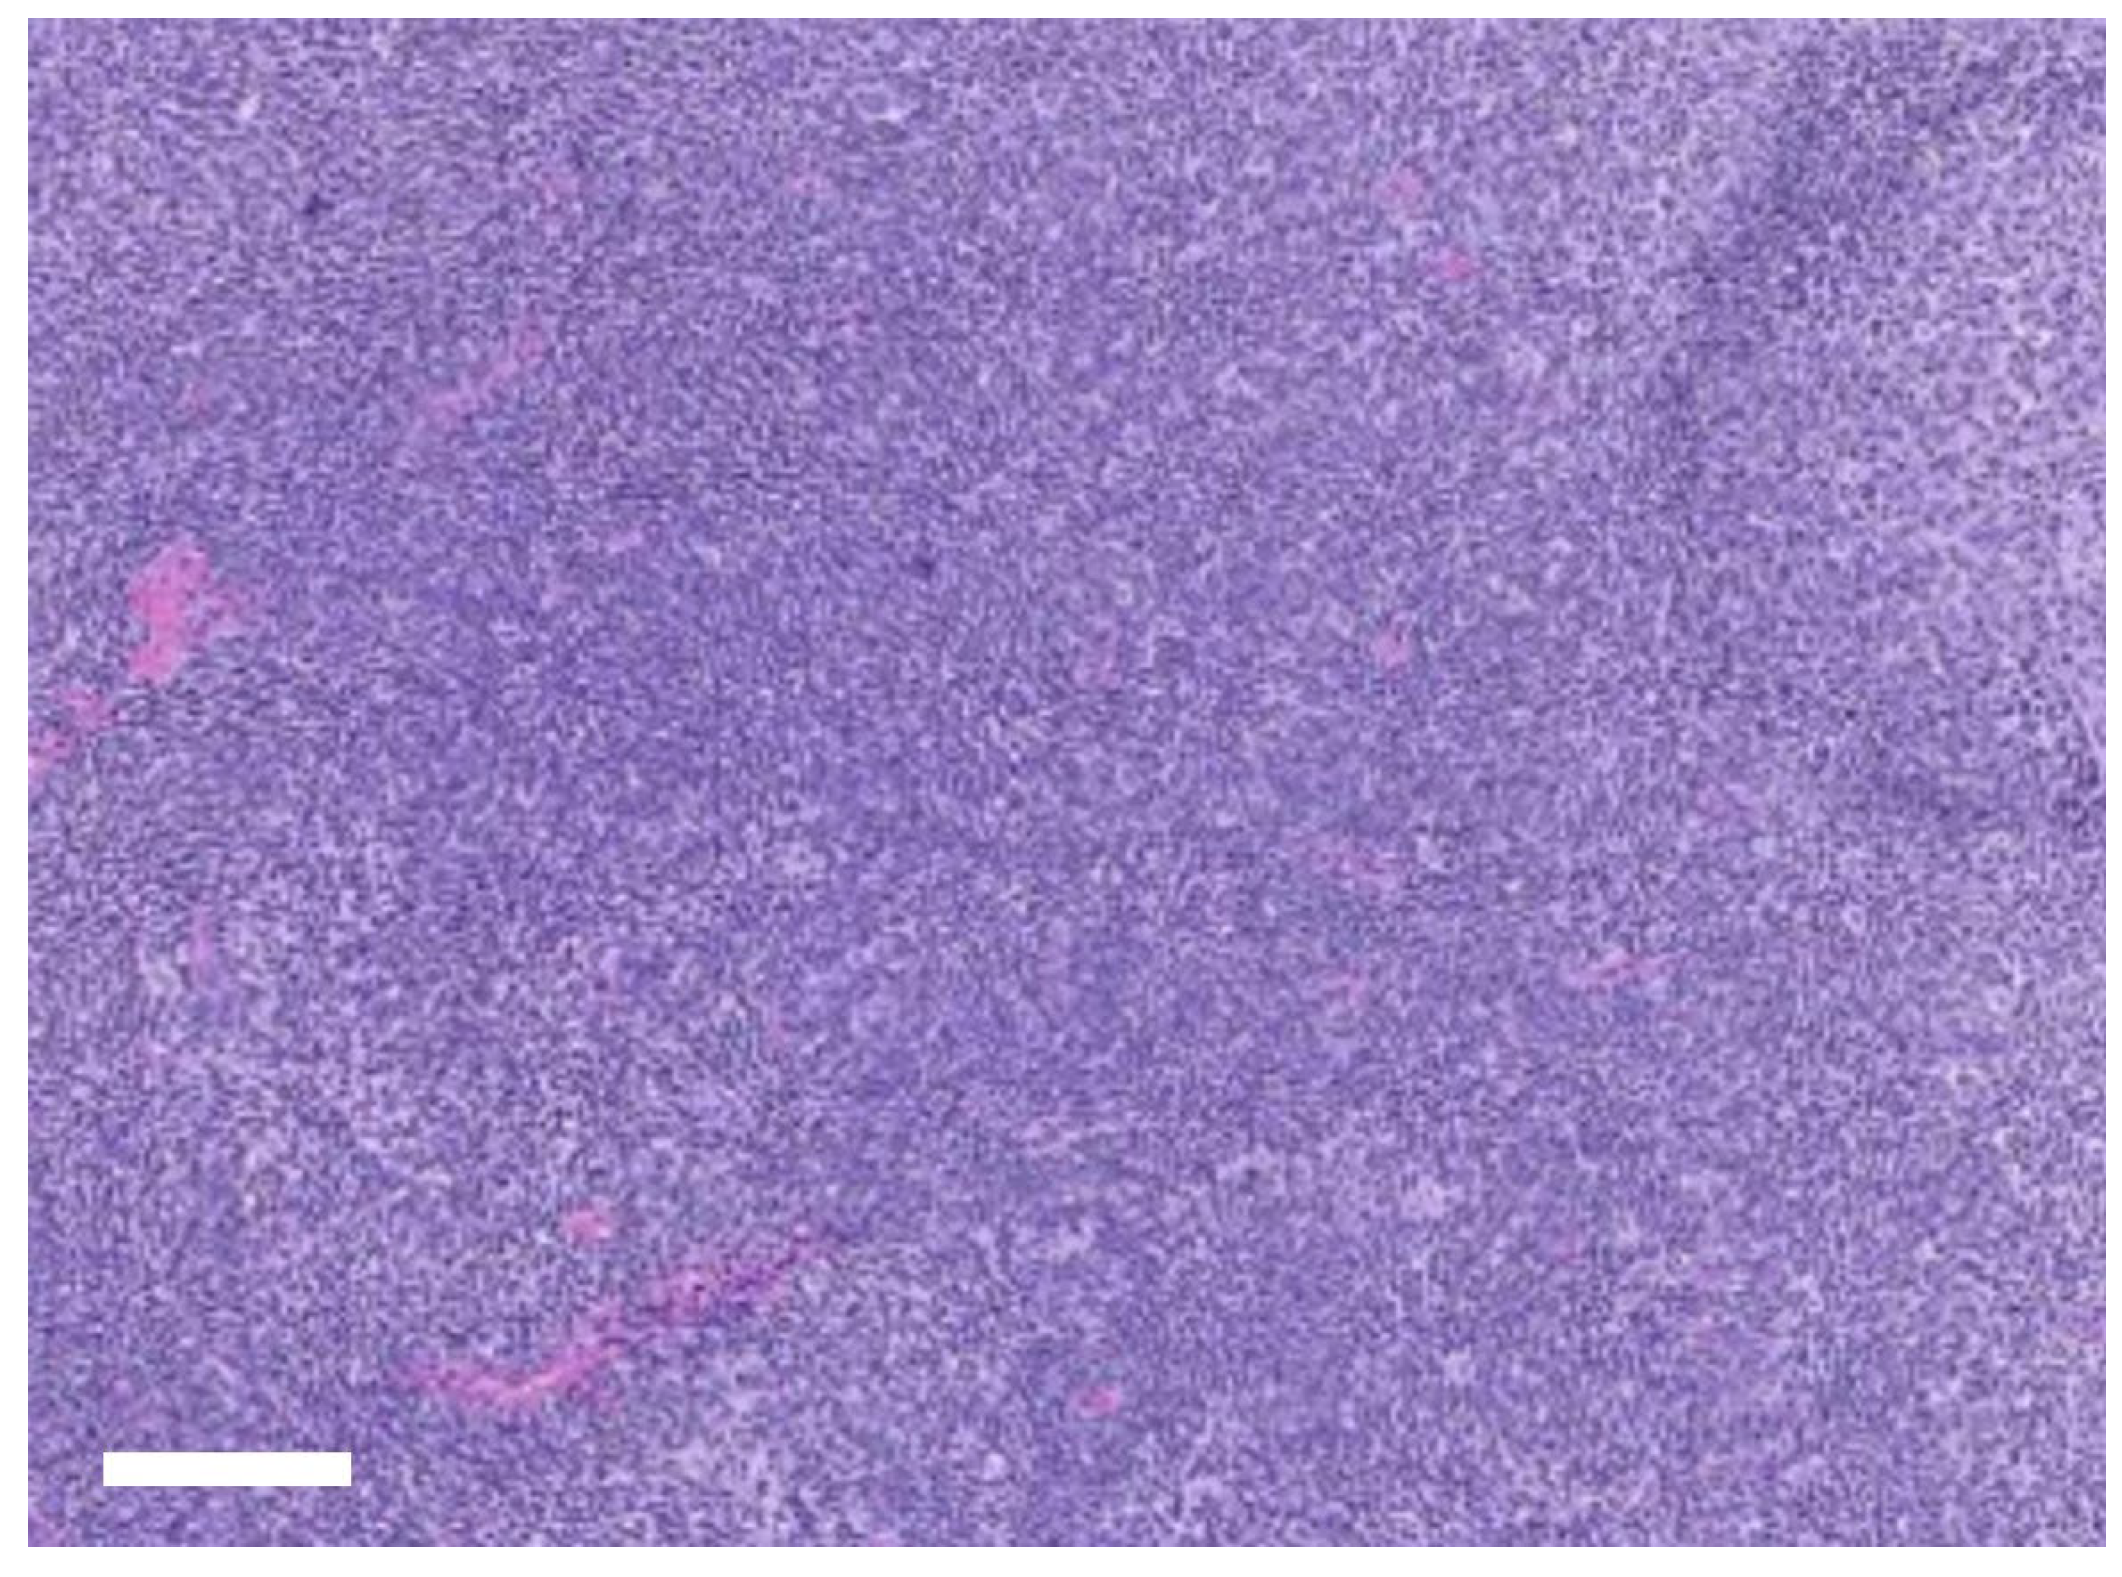

Histopathological examination of the excised right mandibular lymph node revealed diffuse lymphoid hyperplasia (Figure 4), consistent with chronic nonspecific antigenic stimulation and supporting a reactive change rather than neoplasia. The resected lesion also showed chronic inflammatory changes with fibrosis and neutrophilic infiltration, confirming the diagnosis of chronic odontogenic infection associated with cutaneous fistula formation. At the 7-day recheck, the surgical wounds were stable, with no swelling, discharge, or dehiscence, and intraoral healing was satisfactory. The dog maintained a good appetite and activity after extraction. At 2 weeks, sutures were removed without complication, and both intraoral and cutaneous sites had healed well. By 4 weeks, complete resolution of the cutaneous fistula was confirmed, with no pain on palpation and full return to normal feeding and behavior. At the 3-month follow-up, the surgical sites remained stable, with no recurrence of fistula, lymphadenopathy, or inflammation. The owner reported sustained improvements in appetite, comfort, and overall activity levels, indicating a successful outcome.

Histopathology of the excised mandibular lymph node supported a diagnosis of reactive change rather than neoplasia. This finding demonstrated that lymphadenectomy was not only therapeutic in reducing local inflammatory burden but also diagnostically valuable, allowing exclusion of neoplastic disease and confirming chronic antigenic stimulation as the underlying process. By integrating histopathological evaluation into the surgical approach, diagnostic certainty was achieved, thereby justifying the dual intraoral and extraoral intervention [12,13,14].

Figure 4. Histopathology of the excised right mandibular lymph node showing diffuse lymphoid hyperplasia with preserved follicular polarity and tangible body macrophages (H&E, ×100). Scale bar = 100 µm.